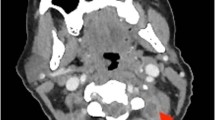

We report two separate cases of SEA in pregnancy and summarize the existing literature. Case 1: A 20-year-old G1P0 presented at 35-week gestation with low back pain and lower extremity (LE) weakness. Magnetic resonance imaging (MRI) revealed thoracic SEA. The patient underwent cesarian delivery followed by posterior thoracic laminectomy and fusion (T9–11), abscess decompression, and antibiotic therapy. Unfortunately, there was a recurrence of her infection requiring a second irrigation and debridement 1 month after index procedure. At final follow-up, the patient had complete neurologic recovery. Case 2: A 38-year-old G10P0 presented at 36-week gestation in labor with LE weakness and difficulty ambulating. After delivery, she had significant LE neurologic deficits. MRI demonstrated thoracic osteodiscitis with associated epidural abscess. She underwent thoracic laminectomy and fusion (T7–12), abscess decompression, and antibiotic therapy. Unfortunately, despite aggressive treatment, she has persistent LE neurologic deficits.